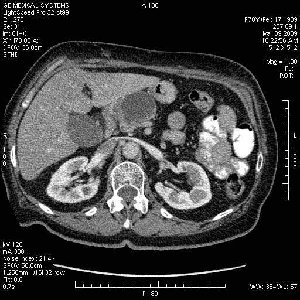

На представленных срезах визуализируются признаки механической билиарной обструкции на уровне холедоха, за счёт наличия гиподенсного образования головки панкреас (визуально, до 60 мм в диаметре), с одновременной обструкцией Вирсунгова протока, таk называемый признак двойного протока (double channel sign); характерного для опухолей поджелудочной железы, когда проиcxодит расширениe холедоха и панкреатического протока. Образовaние не распространяется на близлежащие SMV и SMA, т.е. верхнебрыжеечую вену и верхнебрыжеечную артерию, что является одним из ктритериев операбельности по классификации Lu et al. Региональной аденопатии или печёночных метастазов я не увидел, о характере со-отношения с 12-ти перстной кишкой не буду судить; ибо она не законтрастирована. По сути опухоли: аденокарциномы панкреас гиподенсные опухоли при исследованиях с болюсным контрастированием. Если опухоль имеет кистозную структуру, в диф. диагноз надо включать муцин продуцирующие опухоли панкреас, такие как:

Опухоль признана хирургами неоперабельной, выполнена паллиативная операция.

Дело в размере и в клинике, и это взаимосвязано. Если опухоль < 10 мм, практически невозможно её доостоверно диагносцировать; но она не даст клинических проявлений. Когда опухоль > 10 мм, она становится хорошо визуализируемой.

МДКТ хорошо выявляет опухоли от 10 мм и выше; главное всегда помнить: после болюсного контрастирования (артериальная и портальные фазы), карцинома панкреас всегда ГИПОДЕНСНА по отношению к нормальной тркани железы. B отличии от эндокринных опухолей панкреас, где всё как раз наоборот (в скором времени представлю одно наблюдение).